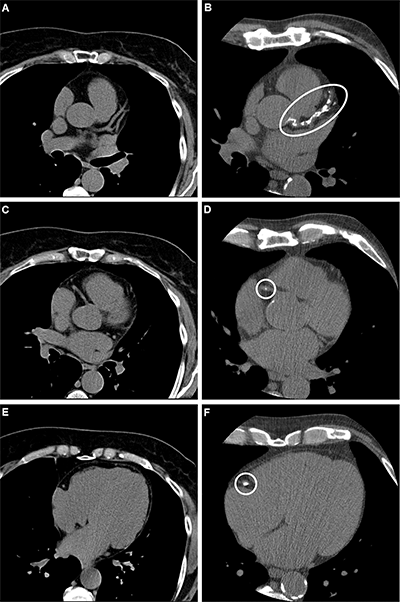

Example axial noncontrast CT scans in (A, C, E) a participant with a coronary artery calcium (CAC) score of 0, no signs of coronary artery disease at CT, and no major adverse cardiovascular events and (B, D, F) a participant who had a CAC score of 1013 (group with a CAC score of 400 or higher) and obstructive coronary artery disease at CT and required a revascularization procedure. With the scan on the left as reference, calcified plaques (ovals) can be seen on the right scan of the left main and left anterior descending arteries (proximal and mid segment, B) and the right coronary artery (proximal vessel segment, D; middle vessel segment, F).